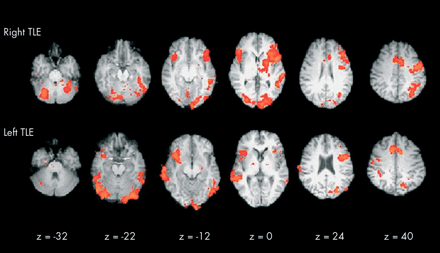

Areas in red show the activation of brain regions when an individual with temporal lobe epilepsy (TLE) carries out a verbal fluency task. Credit: Matthews PM, Jezzard P. Functional magnetic resonance imaging. Journal of Neurology, Neurosurgery & Psychiatry 2004;75:6-12.

fMRI scans

• Function magnetic resonance imaging (fMRI) scanners show which areas of the brain are active by detecting changes in blood flow.

• Brain regions which are stimulated will be respiring more, so more blood will be flowing to these regions (to deliver more glucose and oxygen).

• Oxygenated blood produces a stronger signal in a magnetic field compared to deoxygenated blood, so these areas show up on the fMRI scan.

fMRI scans are similar to MRI scans but they can also be used to research the function of different brain structures. For example, a person inside the scanner may be asked to look at images of different faces. The areas of the brain which light up on the fMRI scan will indicate the brain regions which are involved in facial recognition. fMRI scans are also used in medical diagnosis since they show damaged and diseased parts of the brain.